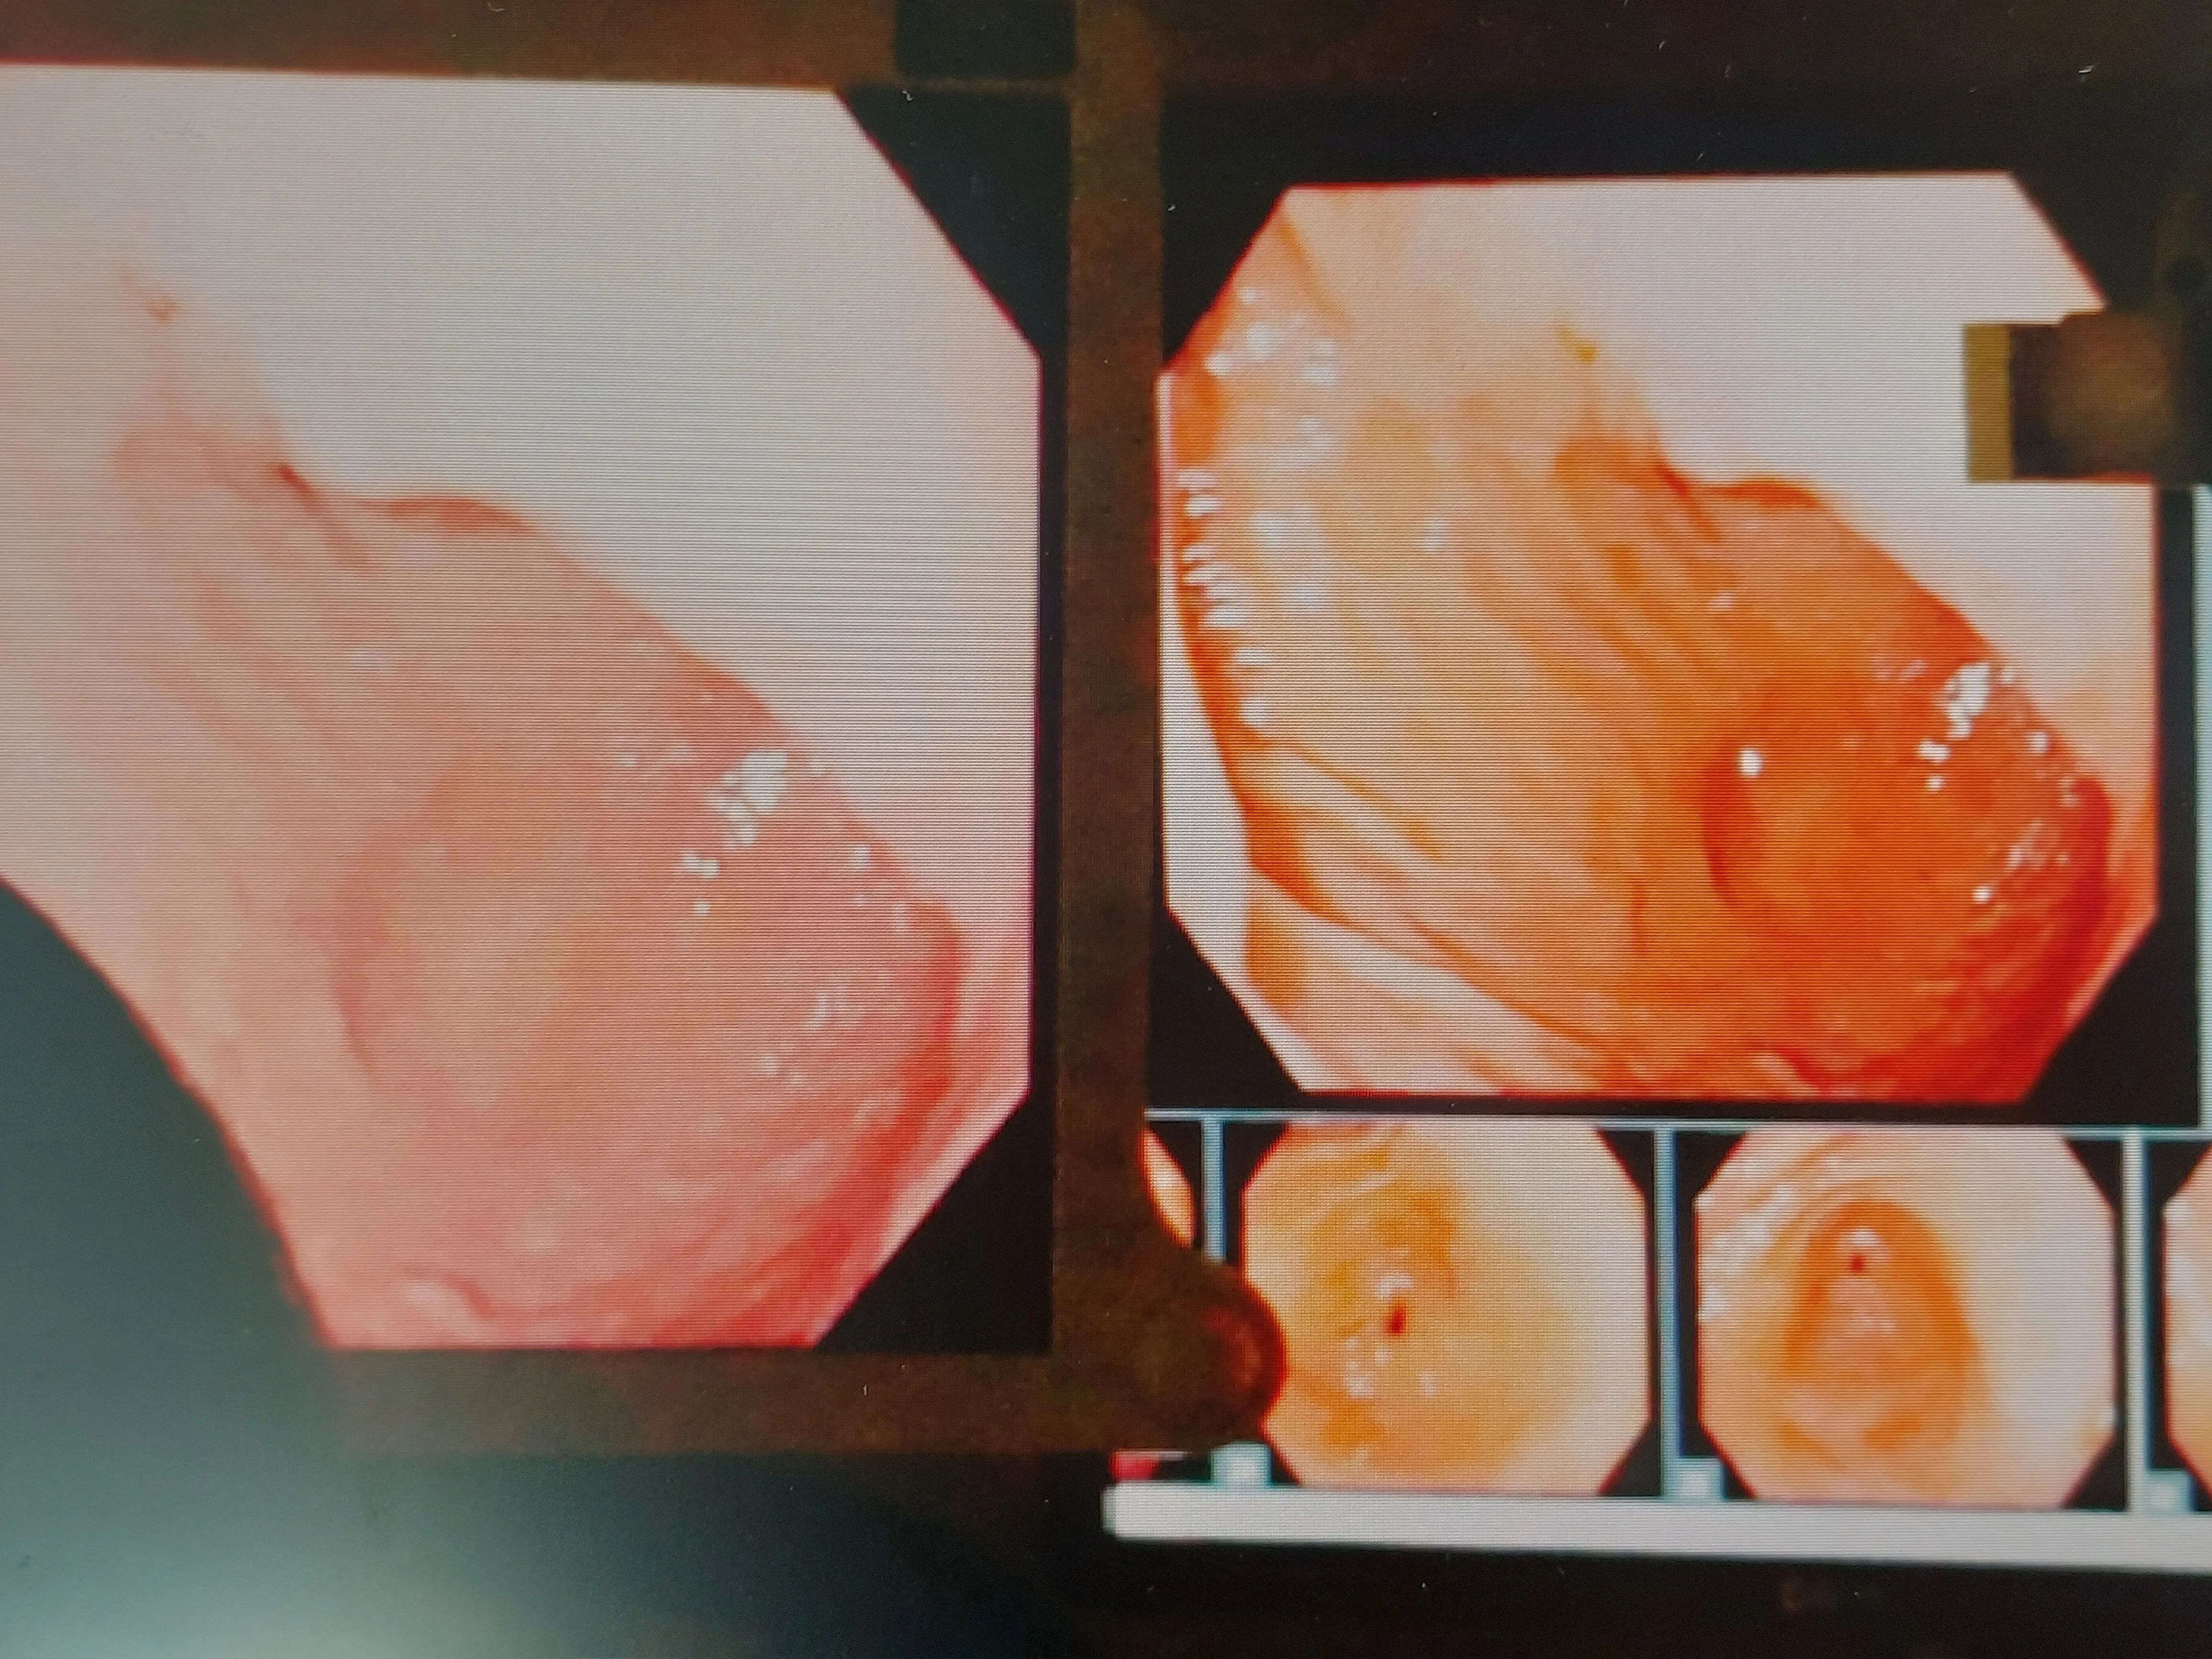

대장 내시경 검사를 준비하고 계신가요? 대장 내시경 검사란 내시경을 사용해서 항문과 직장, 대장 내부를 확인하는 검사인데요. 대장 내시경 검사를 통해 조기에 대장암을 발견하고 예방하기 위해 꼭 필요한 검사 중 하나랍니다.

대장 내시경 검사는 직접 대장 내부를 확인하여 이상이 있는지 여부를 판단할 수 있는데, 이를 통해 조기에 대장암을 발견하고 적절한 치료를 시작할 수 있습니다. 분변 잠혈 검사로도 대장의 건강 상태를 확인해 볼 수 있지만 정확도가 떨어질 수 있다는 의견도 있기 때문에 검사 결과와 상관없이 증상이 있거나 가족력이 있다면 대장 내시경 검사를 받아보는 것이 좋습니다.